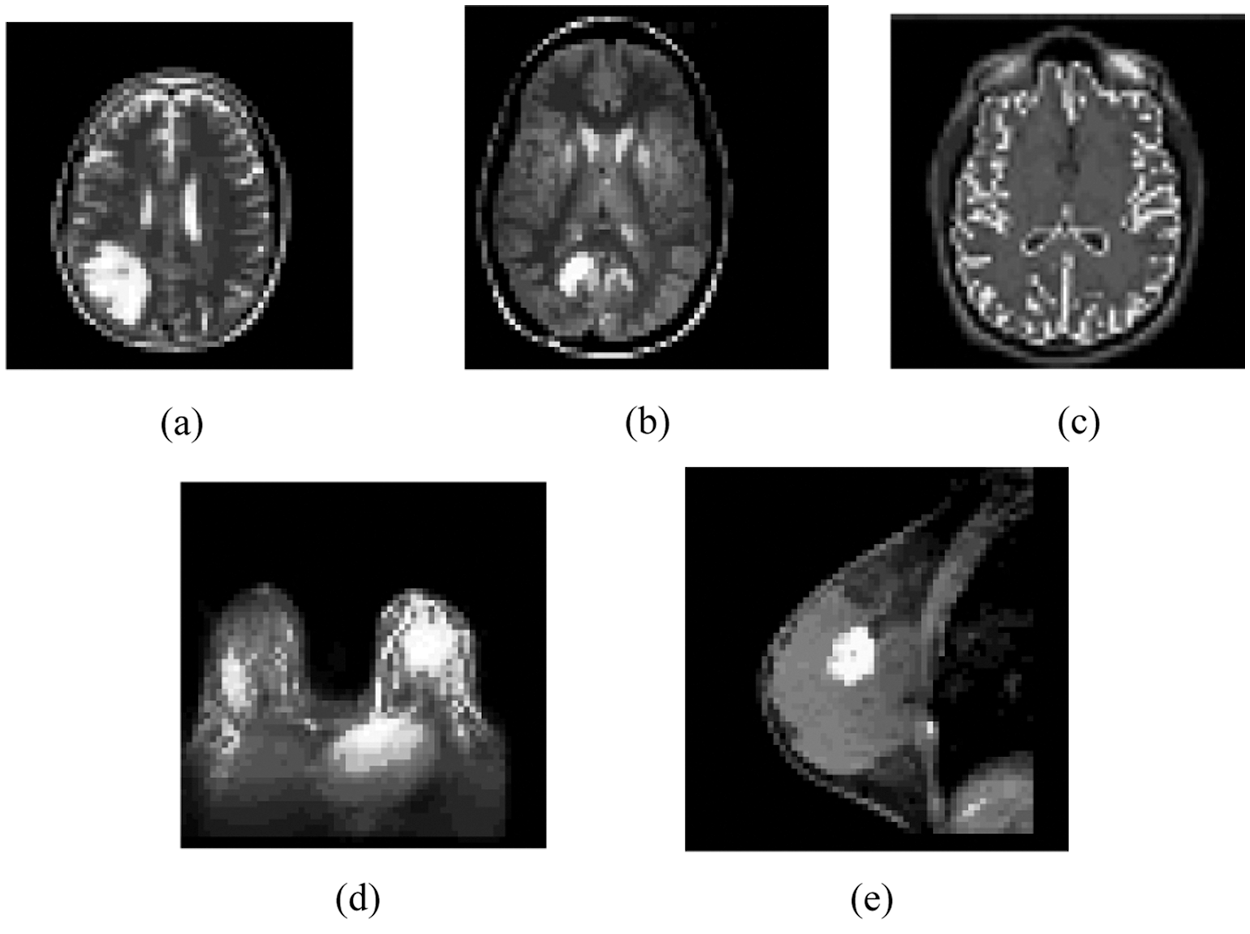

Figure 2: Result of the MIPC scheme tested on the ten gray scale images using iLIAC approach indicated in Fig. 1: (a) Result of brain_1 (b) Result of brain_2 (c) Result of brain_3 (d) Result of breast_1 (e) Result of breast_2

Firstly, the MIPC approach identifies distinct number of dissimilar clusters over the seven gray scale medical image datasets based on iLIAC scheme. Initially, it computes the control merge cost over seven gray scale MR images and the results are obtained in Tab. 1 as 7.87, 7.51, 7.71, 7.85, 7.44 respectively. Then it followed by computation of upper triangular distance matrix and in the case of sample gray scale MRI image datasets are presented in Fig. 2. The clustering scheme could identify 24, 25, 24, 25 and 25 distinct clusters over the MRI images in the Fig. 2. The results are incorporated in the Tab. 1. Fig. 3 demonstrates the clustering result of the iLIAC scheme has tested the MRI images likely Brain_1, Brain_2, Brain_3, Breast_1 and Breast_2 as obtained in Figs. 2a–2e respectively.